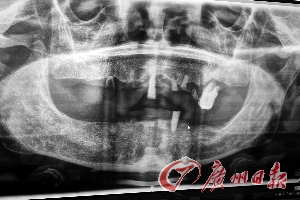

残根、全口牙缺失是高龄老人口腔常态。

大量牙齿缺失,剩下多为残根烂牙,导致很多高龄老人咀嚼力下降,活动牙咬合不稳吃东西松动,严重影响晚年口福。近日,大批缺牙患者报名参加80~99岁老人免费种牙的“羊城口福大行动”,而他们大多镶了活动假牙,但咬合不稳,经常松动甚至脱落,护理上也很繁琐,希望做稳固好用、吃得香的种植牙。

今年82岁的梁老伯在76岁的时候就已是全口无牙,当时做了活动假牙修复,刚开始使用还可以,一般吃饭没问题。近3年来,他的活动假牙松动厉害,一吃东西就脱落,最后只能吃很软的食品——老伴帮他把蔬菜和肉一律打成糊状,“我看到这些,一点胃口都没有,肚子还空着,嘴里又吃不下,不知道是饿还是饱。总之吃饭好似‘上刑场’一样。”到了现在,活动假牙根本无法正常使用,因为一戴就松,一张口就松脱,说话只能吱吱呜呜,不戴假牙时还能说得清楚些,但是脸上很不好看。他一边说一边用手指着因嘴巴周围的凹陷处,尴尬地承认自己的爱牙护牙观念确实薄弱,而这也是他们那一代人的通病。

“像梁老伯这样的患者,在这次活动中还有很多。”Zannar表示,活动假牙具备基本的咀嚼功能,但使用5年左右,咀嚼力就会大大减弱,容易松动脱落,即使重新镶一次活动假牙也是如此。他提醒说,身体是一个有机整体,当牙齿丧失基本的咀嚼功能后,饮食只能以软食为主,如稀饭、面条等,进食需缓慢进行。否则的话,未嚼细的食物进入肠胃,势必加重肠胃的负担,诱发肠胃病,这就是很多缺牙老人常年被胃病困扰的原因。